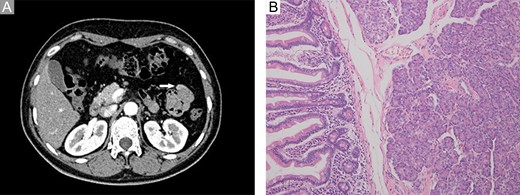

A 46-year-old woman complaining of epigastric pain for 1 month was admitted to our hospital. She denied a history of abdominal diseases or surgeries. Her physical examination results were normal. Laboratory tests, including blood routine tests as well as tests for liver and kidney function, electrolytes, pertinent serum tumor markers, were within the normal ranges except for the levels of carcinoembryonic antigen (CEA) and carbohydrate antigen 72-4 (CA72-4), which were elevated (Fig. 1). Therefore, further tests were performed. Esophagogastroduodenoscopy did not reveal anything abnormal; however, abdominal contrast-enhanced computed tomography (CT) demonstrated a persistently enhanced mass (12 mm × 8 mm in size) in the proximal jejunum (Fig. 2A). Therefore, the patient underwent an exploratory laparotomy owing to a suspicion of malignancy; a solid mass was located approximately 30 cm away from the Treitz ligament and protruded from the serosal surface. Intraoperative exploration revealed no other abnormality. Subsequently, segmental resection of the affected jejunum was performed. Surprisingly, intraoperative frozen section histopathological analysis of the resected specimen revealed pancreatic tissues; postoperative pathological examination of these pancreatic tissues confirmed the presence of jejunal ectopic pancreas containing numerous acini cells in the submucosa and muscular layer; however, malignant transformation or inflammation were not noted (Fig. 2B 200×, H&E). Thus, side-to-side anastomosis rather than extended resection was performed. More surprisingly, serum levels for the two tumor markers (CEA and CA72-4) decreased to normal levels when rechecked on the fifth day postoperatively (Fig. 1). The patient was discharged on the sixth day postoperatively, and no abnormality was noted during 6 months of follow-up.

Imaging and pathological examination findings. (A) Computed tomography scan revealed a persistently enhanced mass (approximately 12 mm × 8 mm in size) located at the proximal jejunum (white arrow). (B) Histological diagnosis revealed ectopic pancreas dominated by acini within the submucosa and muscular layer; however, no malignant transformation or other complications were observed (200×, H&E).

Jejunal masses are usually diagnosed via imaging findings rather than digestive endoscopy before surgery owing to their peculiar location. The imaging features of ectopic pancreas correlate with its histologic composition. Lesions dominated by acini exhibit an enhancement greater than or similar to that of the orthotopic gland, whereas lesions dominated by ducts and hypertrophied muscle are less enhanced [2]. The jejunal mass in this case was dominated by acini and manifested as a persistently enhanced structure on an abdominal contrast-enhanced CT scan, which was similar to the findings for certain malignancies. The changes in serum CEA and CA-724 levels further increased the suspicion of malignancy. However, ectopic pancreas was the definitive diagnosis. Thus, the preoperative diagnosis of a jejunal mass should be made cautiously and intraoperative frozen section histopathological analysis of the resected specimen should be performed in a timely manner in order to avoid unnecessary extended resections and worries among patients and their families.